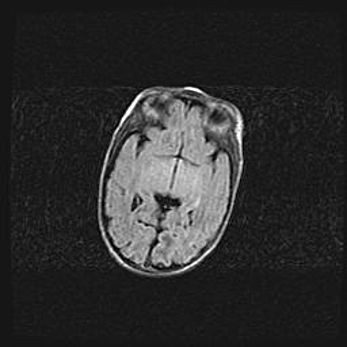

Неполная лизэнцефалия (пахигирия). Открытая гидроцефалия.

Возраст: 17 дней

Вес: 3110 г

Пол: мужской

Окружность головы: 33,5 см

Срок гестации: 35-36 недель

Лизэнцефалия—недоразвитие корковой пластинки и мозговых извилин в результате нарушения миграции нейронов коры. Поверхность мозговых полушарий гладкая. Микроскопически выявляется отсутствие нормальных слоев коры и скопление групп нейронов в подкорковом белом веществе.

Пахигирия—уменьшение числа вторичных извилин. В пораженном полушарии нервные клетки образуют толстый недифференцированный слой с неправильно расположенными нервными волокнами и группами гетеротопных клеток. Нервные клетки незрелые. Белое вещество истончено. При этом нередко аномально развит корково-спинномозговой путь.